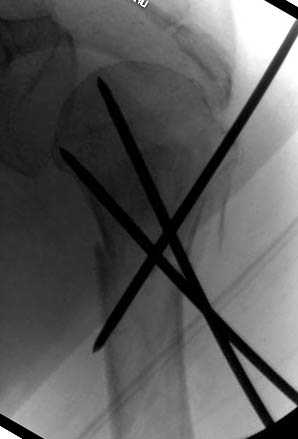

Наш недавний случай перкутанной фиксации "методом

Сиэтла" спицами 2.8 мм с резьбой на конце.

Головка плечав небольшом варусе или это проекционное?

-Головка плеча в небольшом варусе или это

проекционное?

Да, там имеем небольшой варус, надеемся, что в будущем проблемы не будет.

Из-за большого обьема конечности доступ к бугорку был затруднен, предварительно зафиксированный шуруп не удержал бугорок, поэтому фиксацию провели толстыми нитками. Состоятельность фиксации бугорка обычно проверяем во время операции, под рентген контролем проводится движения конечности, особенно приведение.